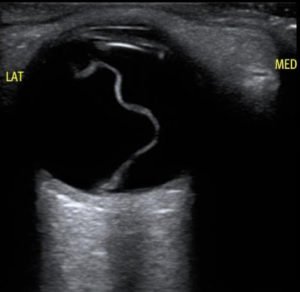

Macula-Off Retinal Detachment. US. UnAnnotated. JETem 2019

Macula-Off Retinal Detachment Identified on Bedside Ultrasound